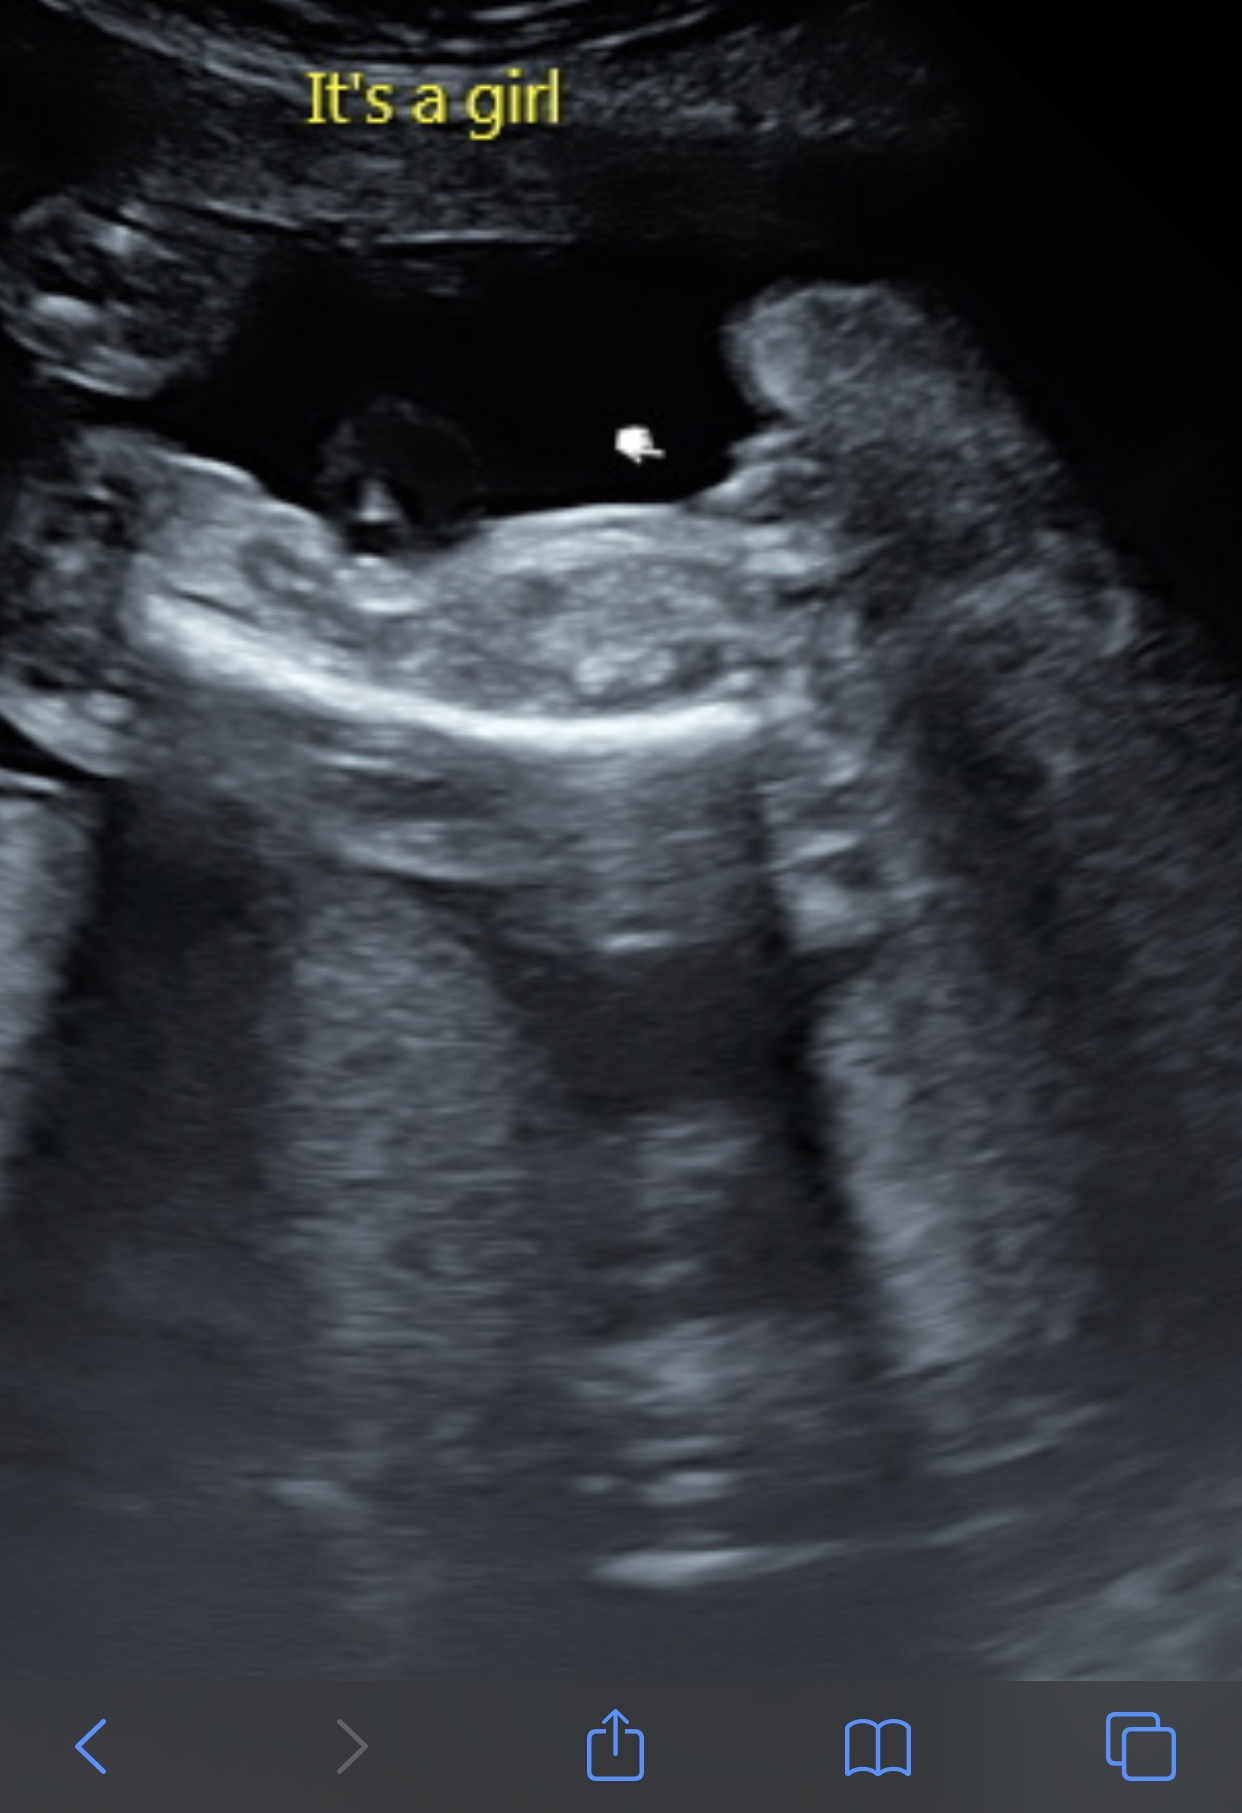

Thank you hun I now have this potty shot if anyone can help x

23 weeks hun xx

Still not able to have a guess unfortunately. Anu nub pictures you can post would be a great help, from maybe the 12-13 week point if you have any :agree:

I will give a very VERY VERY tentative pink lean but the pictures are very small on my screen and I may not be seeing something that is there.

I’m Leaning towards a girl!

Girl from potty shot

girl

Been confirmed a girl 💝💝💝 would you guys say definitely a girl ?xx

Looks girly to me.